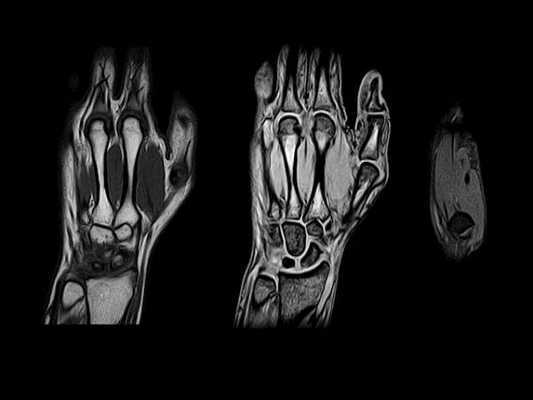

МРТ при переломе запястья

Травмы лучезапястного сустава и кисти – самая распространенная причина проведения МРТ кисти. При лечении перелома в ходе хирургического вмешательства требуется точная репозиция отломков, сшивание сухожилий, нервов. Изучают состояние лучезапястного сустава на МРТ, запястья, пястных костей и пальцев, окружающих их тканей.